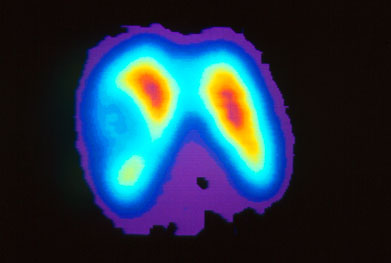

supervivencia libre de progresion en tiroides con vandetanib